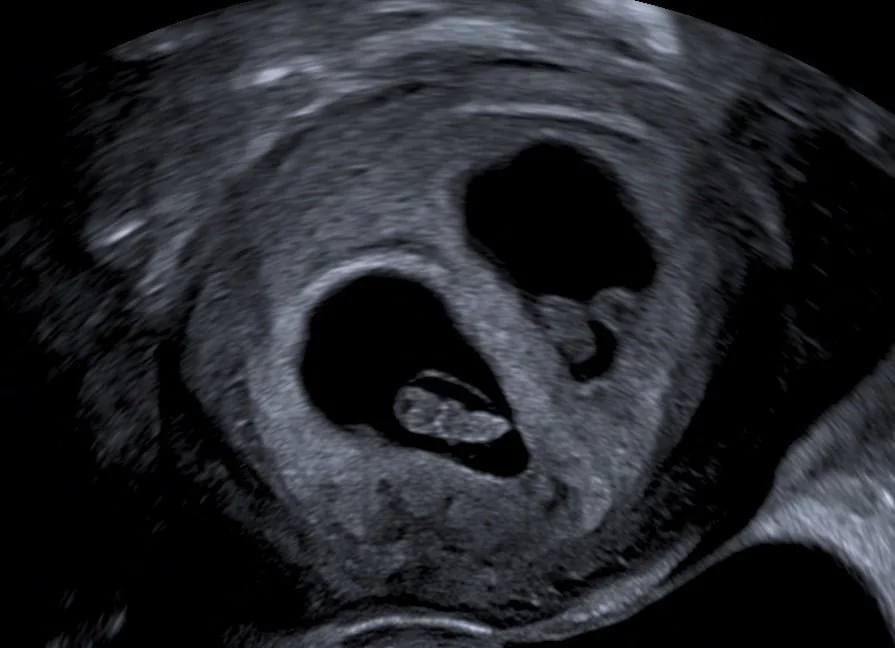

Betreuung von Mehrlingsschwangerschaften, inkl. aller notwendiger Ultraschalluntersuchungen

kombiniertes Ersttrimesterscreening mit Risikoberechnung für früh in der Schwangerschaft auftretende Bluthochdruckkomplikationen sowie die häufigsten Chromosomenstörungen beim Kind zwischen 11+0 – 13+6 SSW. Diese Untersuchung beinhaltet immer auch eine frühe Fehlbildungsdiagnostik des Kindes.

Feindiagnostik 19+0-21+6 SSW., erweitertes Organscreening des Kindes, Beurteilung der Plazenta, Fruchtwasser, Gebärmutterhals, Durchblutung

High-End-Ultraschall

Ich arbeite mit einem „High-End-Ultraschallgerät“ der neuesten Generation, welches speziell für Pränataldiagnostik und Frauenheilkunde entwickelt wurde.